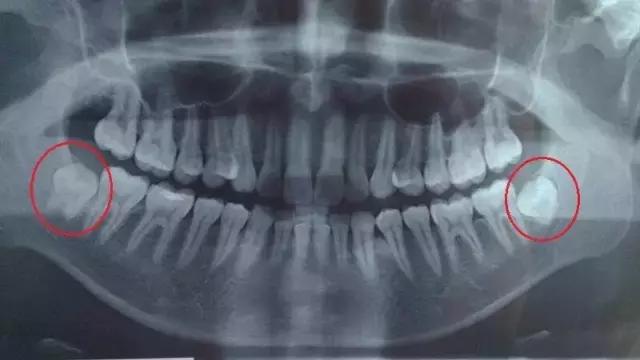

这种情况下的智齿,患者不容易感受到,通过X光照射就能很清晰地看见。

○ 阻生智齿

阻生智齿通常都埋在牙槽骨里面,病人长了这种智齿不一定有感觉。

因而非常容易被忽略,但可通过拍X光片诊断出。

如果感觉到痛,或是通过口腔检查和X光片诊断有病灶发生,那就需要拔除。